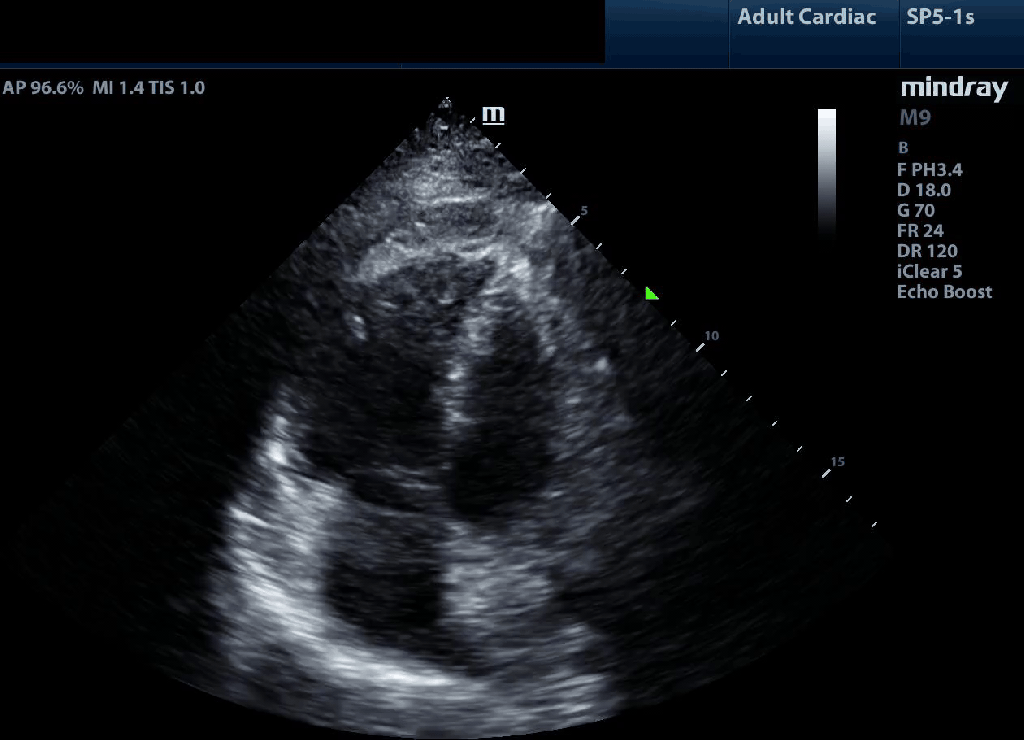

Though not performed in the context of POCUS given its time consuming nature we borrow from the concept of fractional area change (FAC) for RV function estimation. FAC requires tracing the border of the RV endocardium excluding trabeculae during end diastole (left image below) and end systole (right) and calculatin the delta as a percentage of end diastolic area. FAC of <35% is consistent with impaired RV function. We use the principle of this to judge whether the area changes substantially or minimally over the cardiac cycle.